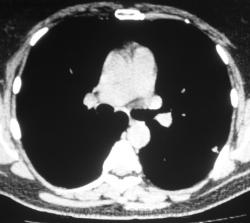

Произведена КТ.

КТ хотелось бы посмотреть в dicom-формате, меняя режимы, но на мой взгляд образование содержит известковые включения. Хотя, я не настаиваю, дождемся мнения коллег.

Нет "волшебных методов", можна поставить диф. ряд. Я бы дала такое заключение: хондрогамартрома, дифференцировать с туберкуломой, периферический рак менее вероятен. Можно жизнь прожить с гамартромой, а может озлиться в саркому. На практике был случай, когда лет 10 наблюдалась классическая скиалогически туберкулома, которая за полгода выросла и оказалась аденокарциномой. Таким образом, при любом раскладе, хирургическое лечение не является ошибкой, но решение об операции на легком должен принимать консилиум.

Дело не в желании, а в смысле. Что тут ещё можно сказать? На мой взгляд-мелкая, частично кальцинированная туберкулома.

Да, более туберкулёма.